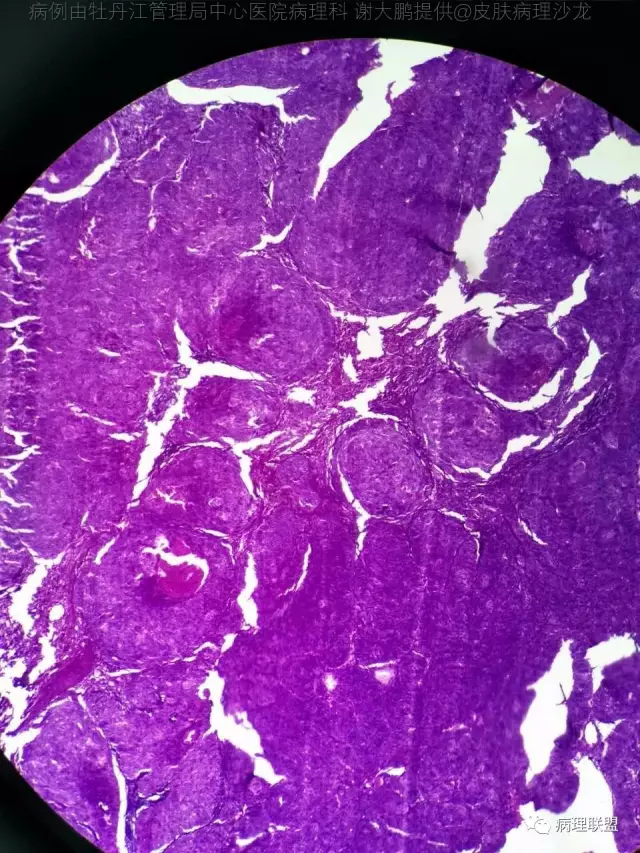

69岁,鼻翼肿物2年,1.5厘米大小,麻烦老师们帮忙看看,谢谢(病例由牡丹江管理局中心医院病理科 谢大鹏提供,致谢!)